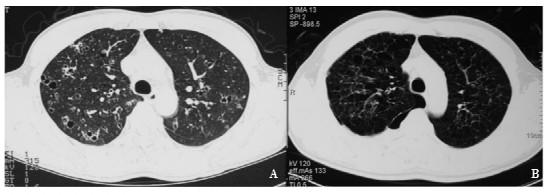

肺郎格罕细胞组织细胞增多症1例